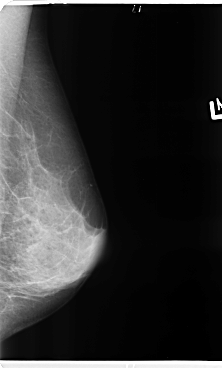

B_3363_1.LEFT_MLO

B_3363_1.LEFT_CC

LEFT_CC LINES 4744 PIXELS_PER_LINE 2680 BITS_PER_PIXEL 12 RESOLUTION 50 NON_OVERLAY

LEFT_MLO LINES 4776 PIXELS_PER_LINE 2880 BITS_PER_PIXEL 12 RESOLUTION 50 NON_OVERLAY